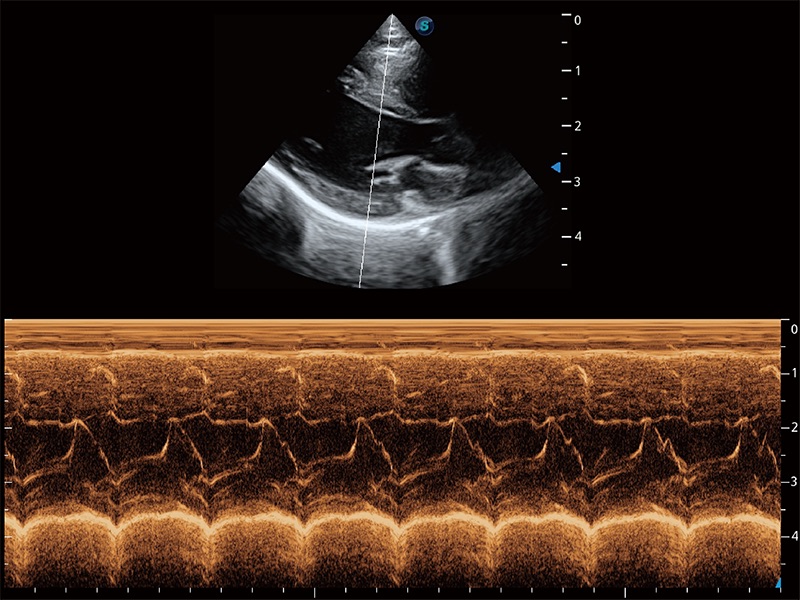

ProPet 80 配备了丰富的心脏探头群、先进的成像技术和专业的心脏测量工具,可帮助动物医生为不同体型和生理结构的动物提供心脏和心肌功能的全面评估。

通过360度任意调节3条M型取样线,在同一心动周期上观察心脏不同位置的运动曲线,得到准确的心功能测量数据,有效评估心肌运动及左心室功能。